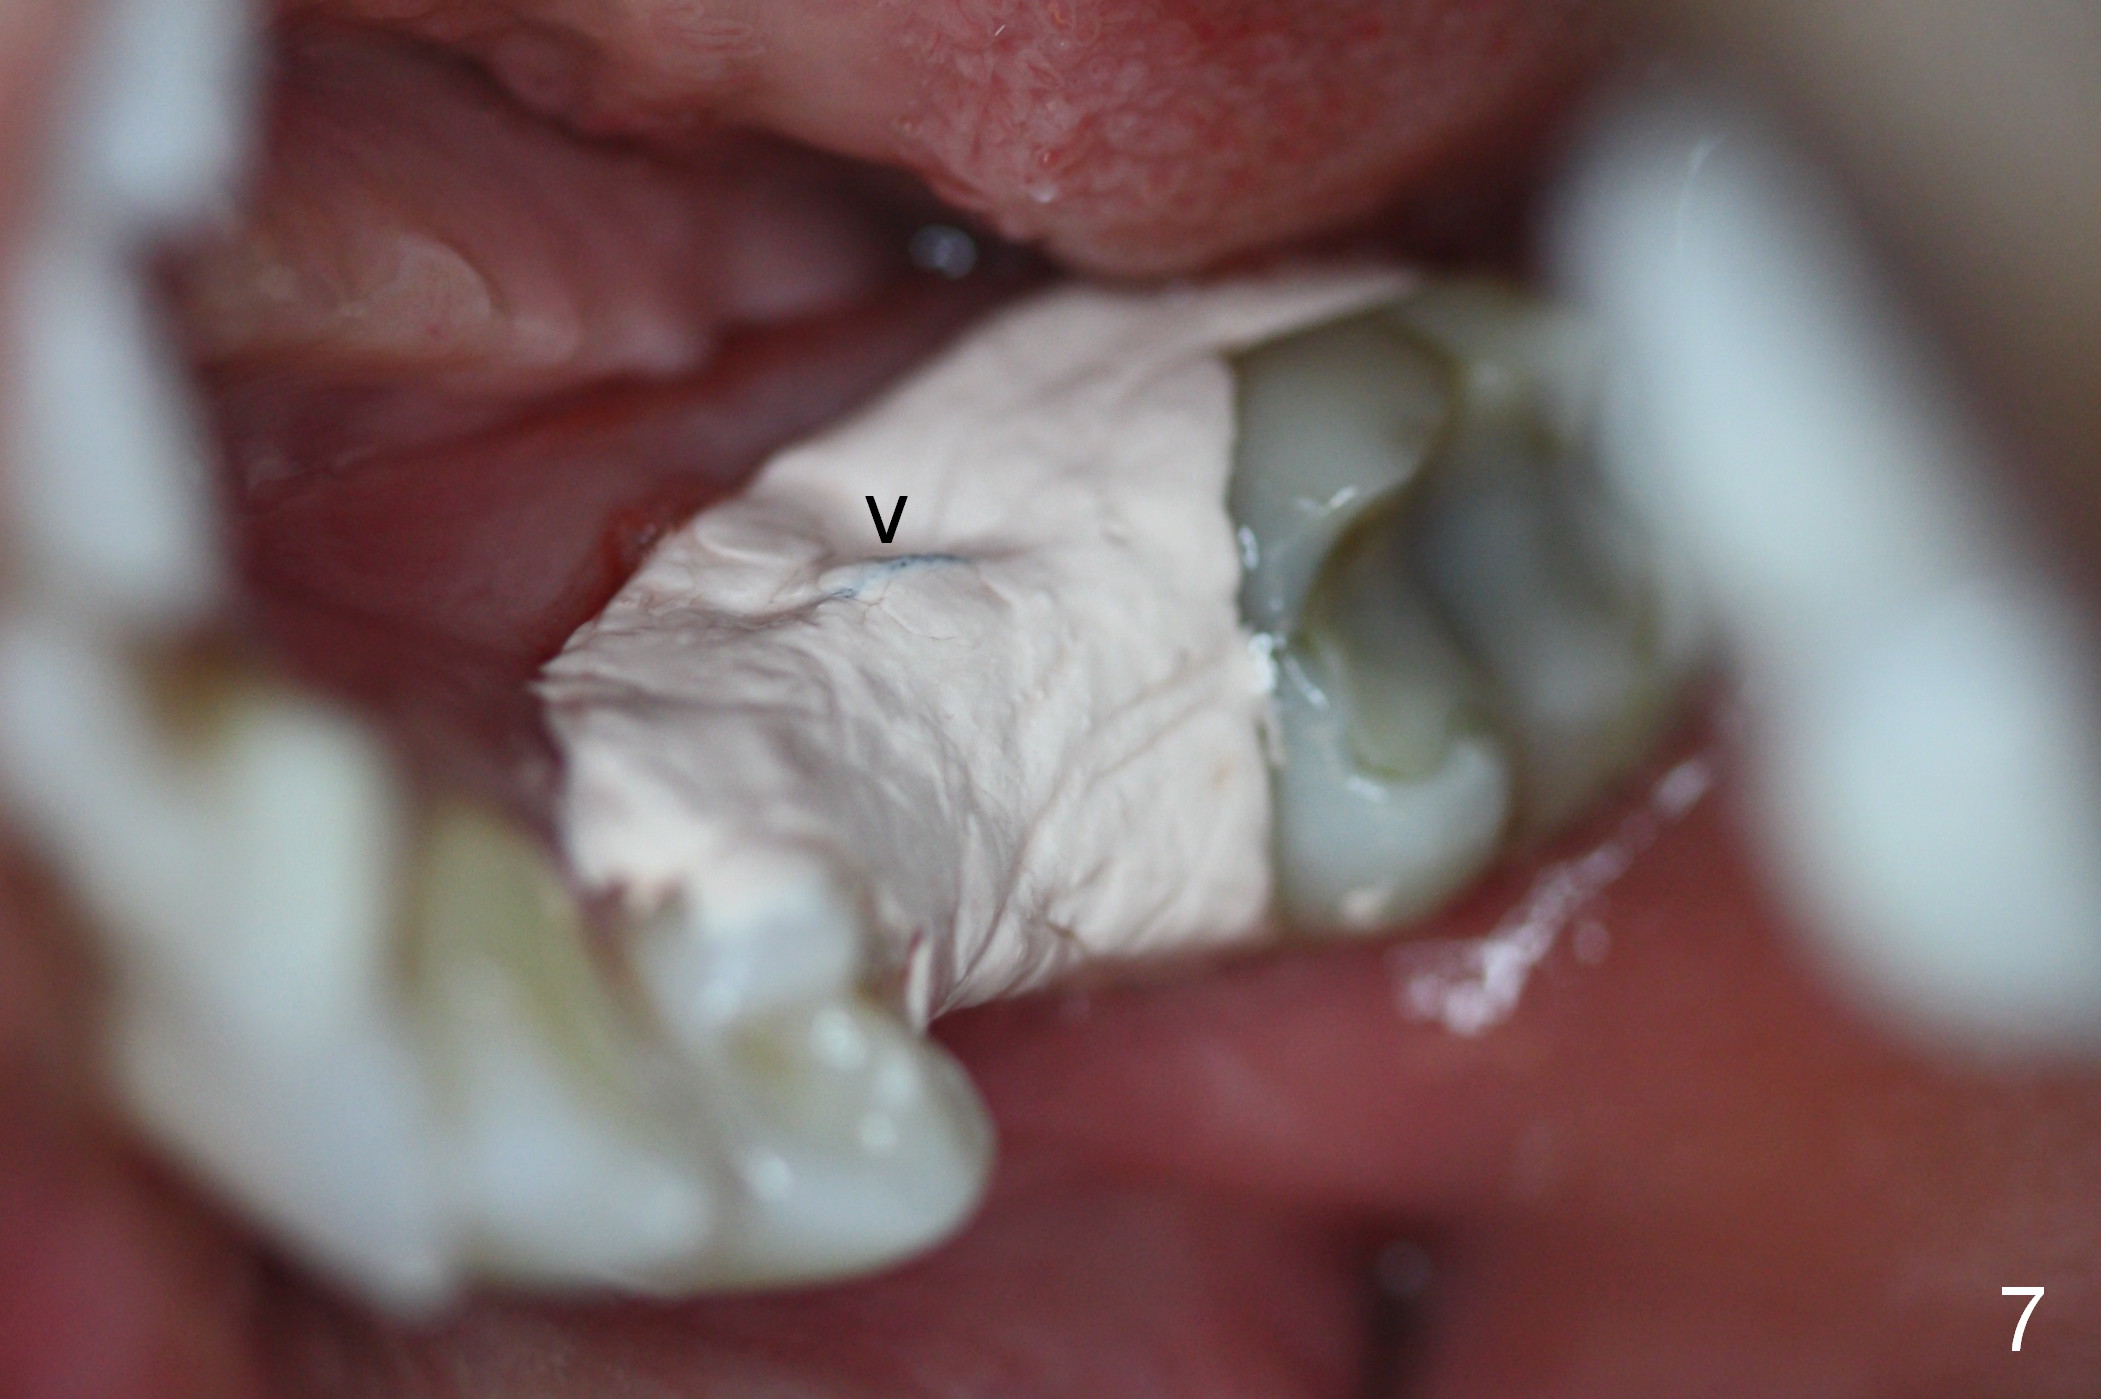

A 44-year-old black lady is a typical dental phobic. She has lost #19 for years with history of traumatic extraction. The ridge is atrophic (Fig.1). She is not comfortable with intraoral X-ray. So CBCT is taken. The coronal section shows that the bone density is low in the coronal ridge (Fig.2 arrowheads). It is difficult to determine the buccolingual width at crest; probably a 5.9x10 mm implant is appropriate (Fig.3). The most useful information from CT is height determination for the implant (Fig.4). The initial osteotomy depth is 10 mm (Fig.5); there is a large safety margin. There is a 2 mm clearance when a 4.5x12 mm implant is placed (Fig.6). Incision is sutured; a 8x4 (3) mm healing abutment is placed (Fig.7 arrowhead), followed by application of perio dressing. The latter remains stable 13 days postop thanks to the holding effect of the healing abutment (Fig.8 H). The wound has apparently healed when the dressing is removed (Fig.9). It appears that the edentulous space is extremely wide. The 4.5 mm implant may not sustain masticatory force. Limited orthodontic treatment appears to be necessary, using the implant as an anchorage to move the neighboring teeth (Fig.10 arrows). In fact the orthodontic treatment is not rendered. A crown is cemented 14 months postop. The cortical bone is thickened around the implant 15 months post cementation (Fig.11).